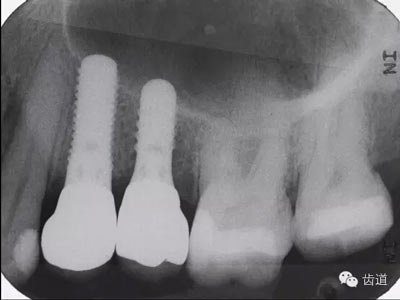

將診斷模型上HE架,就是為了上述這些步驟。上了HE架之后,我們可以評(píng)估患者的咬合關(guān)系,種植體植入的位置,以及應(yīng)力方向等許多重要因素。我們還可以在HE架上判斷種植體上部修復(fù)體的制作方式,例如是否使用角度基臺(tái)(圖1)。

1.jpg

圖1:種植治療方案計(jì)劃

過程中的錯(cuò)誤會(huì)直接影響上下牙弓間距離,咬合接觸和應(yīng)力方向的判斷(圖1,4)。這些判斷的錯(cuò)誤會(huì)直接影響到正確的診斷,治療計(jì)劃的制定,種植體類型的選擇,基臺(tái)的角度選擇以及修復(fù)體的設(shè)計(jì)。

VF軟件也可以記錄上下頜之間的咬合關(guān)系,這對(duì)于將模型精確的上HE架很重要,所以對(duì)于復(fù)雜的種植病例(圖15),VF軟件也可以勝任將HE關(guān)系轉(zhuǎn)移至HE架的工作。HE架上的模型位置精確,種植體植入的位置和角度才能準(zhǔn)確(圖16)。

15.jpg

圖15:種植病例

16.jpg

圖16:種植體X片